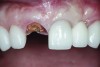

Fig 2. Periapical radiograph revealing the fractured central incisor.

Figure 2

A 63-year-old female patient presented with mobility of her right maxillary incisor, tooth No. 8, secondary to endodontic therapy (Figure 1). Her medical and dental histories were non-contributory. Clinical and radiographic evaluations revealed an 8-mm probing depth on the palatal aspect. The tooth was deemed to be fractured (Figure 2). The treatment plan accepted by the patient was for extraction, immediate implant placement, and immediate provisional restoration, if possible.